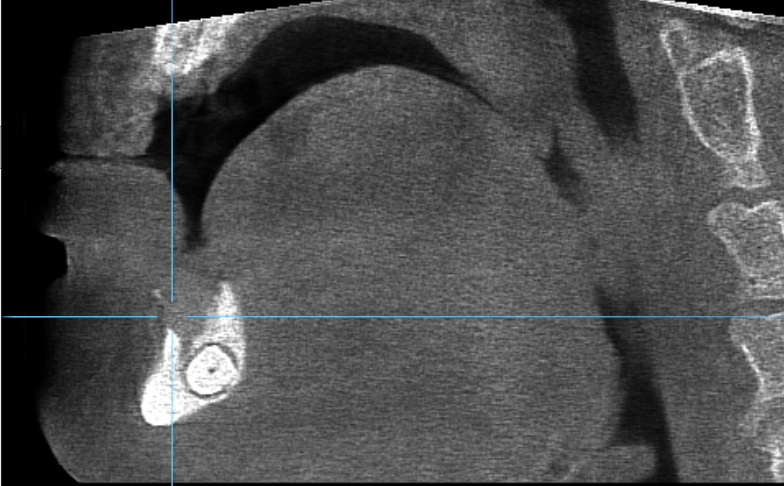

Streszczenie: Przewlekłe zapalenie kości jest schorzeniem sprawiającym wiele trudności zarówno w diagnostyce, jak i leczeniu. Co więcej, zapalenie kości jest uznawane za chorobę na całe życie ze względu na jej częste wznowy. Praca prezentuje przypadek pacjenta, który zgłosił się z obrzękiem oraz bólem umiejscowionym w okolicy bródki. Wykonana tomografia stożkowa wykazała obecność zmian osteolitycznych oraz zagęszczeń struktury kostnej w okolicy przedniej części żuchwy. Zmiany były połączone z kłem, który uległ transmigracji. W pierwszej części leczenia wykonano odbarczenie ropnia poprzez nacięcie zewnątrzustne oraz drenaż. W drugiej fazie zabiegu przeprowadzono zabieg usunięcia martwiczych tkanek oraz ziarniny zapalnej. Ostatecznie przeprowadzono atraumatyczną ekstrakcję zatrzymanego kła.

Summary: Chronic osteomyelitis is a disease difficult to diagnose and treat. Moreover, osteomyelitis is considered to be a disease of the whole life, due to its frequent recurrences. The paper presents a case of a patient with pain and swelling localized around the chin. The CT revealed the presence of osteolysis and places of increased [...]